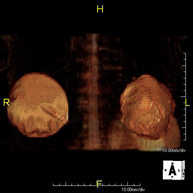

Prova diagnòstica no invasiva que consisteix en l'obtenció d'imatges d'alta definició anatòmica del fetge mitjançant l'ús d'un camp electromagnètic i ones de ràdio (amb un emissor i un receptor). No utilitza radiació ionitzant. Es realitza per estudiar qualsevol lesió localitzada en el fetge. Normalment es requereix l'ús de contrast paramagnètic (Gadolini) per caracteritzar les lesions. És necessari realitzat la prova en dejú (6 hores). - RM de Ronyons

Prova diagnòstica no invasiva que consisteix en l'obtenció d'imatges d'alta definició anatòmica d'ambdós ronyons mitjançant l'ús d'un camp electromagnètic i ones de ràdio (amb un emissor i un receptor). No utilitza radiació ionitzant. Es realitza per estudiar qualsevol lesió localitzada en ambdós ronyons. Normalment es requereix l'ús de contrast paramagnètic (Gadolini) per caracteritzar les lesions. - RM Glándulas Suprarrenales